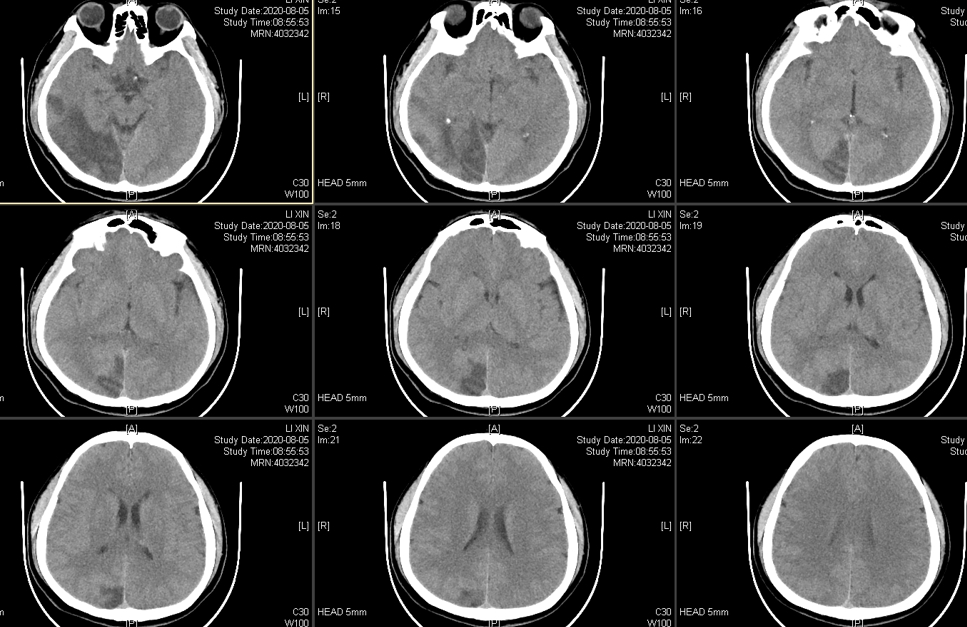

CT显示为右侧颞枕叶脑梗塞,同时累及了大脑中动脉和大脑后动脉分布区。

出血时CT: